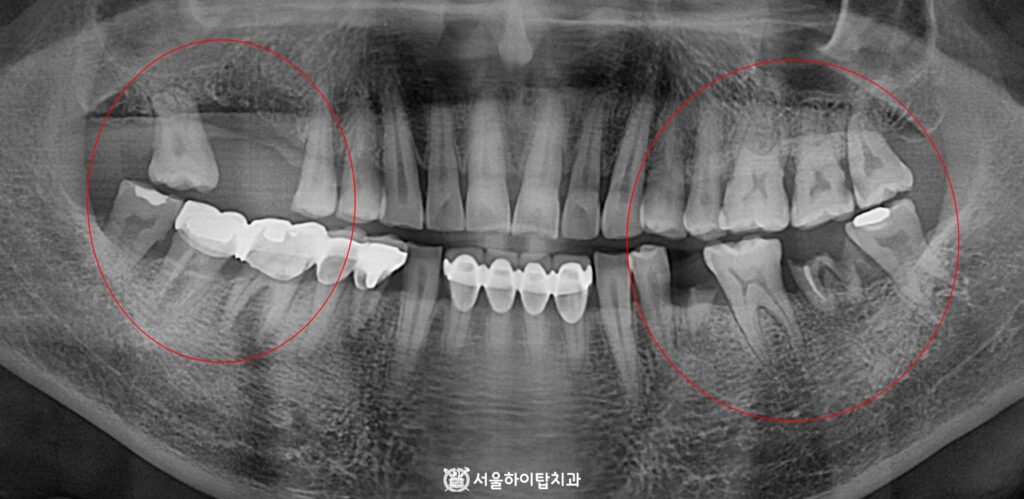

초진

초진 파노라마 엑스레이를 확인해 보면 한눈에 보더라도

상실되고 심하게 훼손된 자연치를 확인할 수 있습니다.

즉, 이는 앞서 부평 치과 에서 말씀드린 골 흡수, 인접치 이동 문제가 나타날 수 있는 소견으로,

실제로 위 사진을 보면, 골 흡수와 사랑니가 점점 기울어지는 모습을 관찰할 수 있습니다.

또한, 반대쪽 어금니는 치근만 남아있는 ‘잔존치근'(Root Rest) 상태로,

저작 활동이 제한되기 때문에 교합 관계가 불안정한 상태임을 알 수 있습니다.